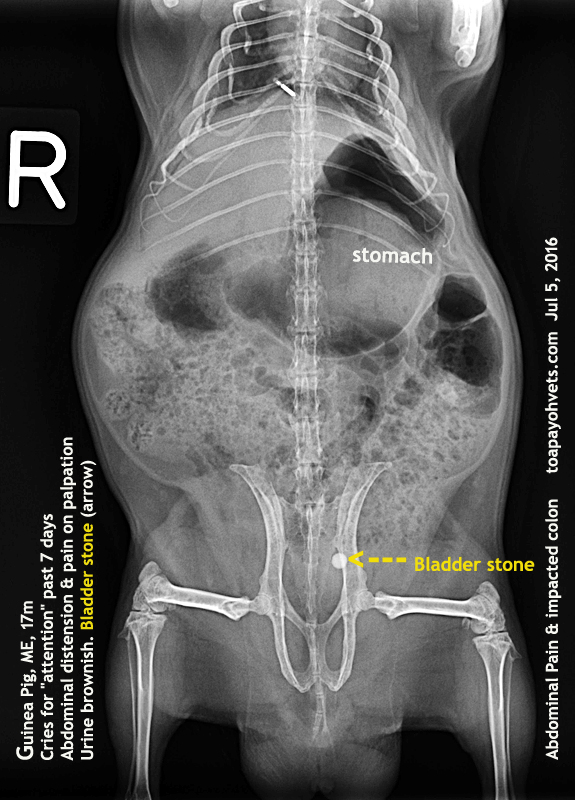

From 2010vets.blogspot.com

Be Kind To Pets, Vet case studies, Photography tips, Travel Stories What To Feed Guinea Pig With Bladder Stones Bladder stones in the urethra can sometimes. if a guinea pig has a bladder stone, it may recur several months later if the guinea pig is genetically predisposed to stone. the best vegetables for guinea pigs with calcium deposits or bladder stones/sludge are veggies low in calcium, high in water, and ideally high. according to one study,. What To Feed Guinea Pig With Bladder Stones.